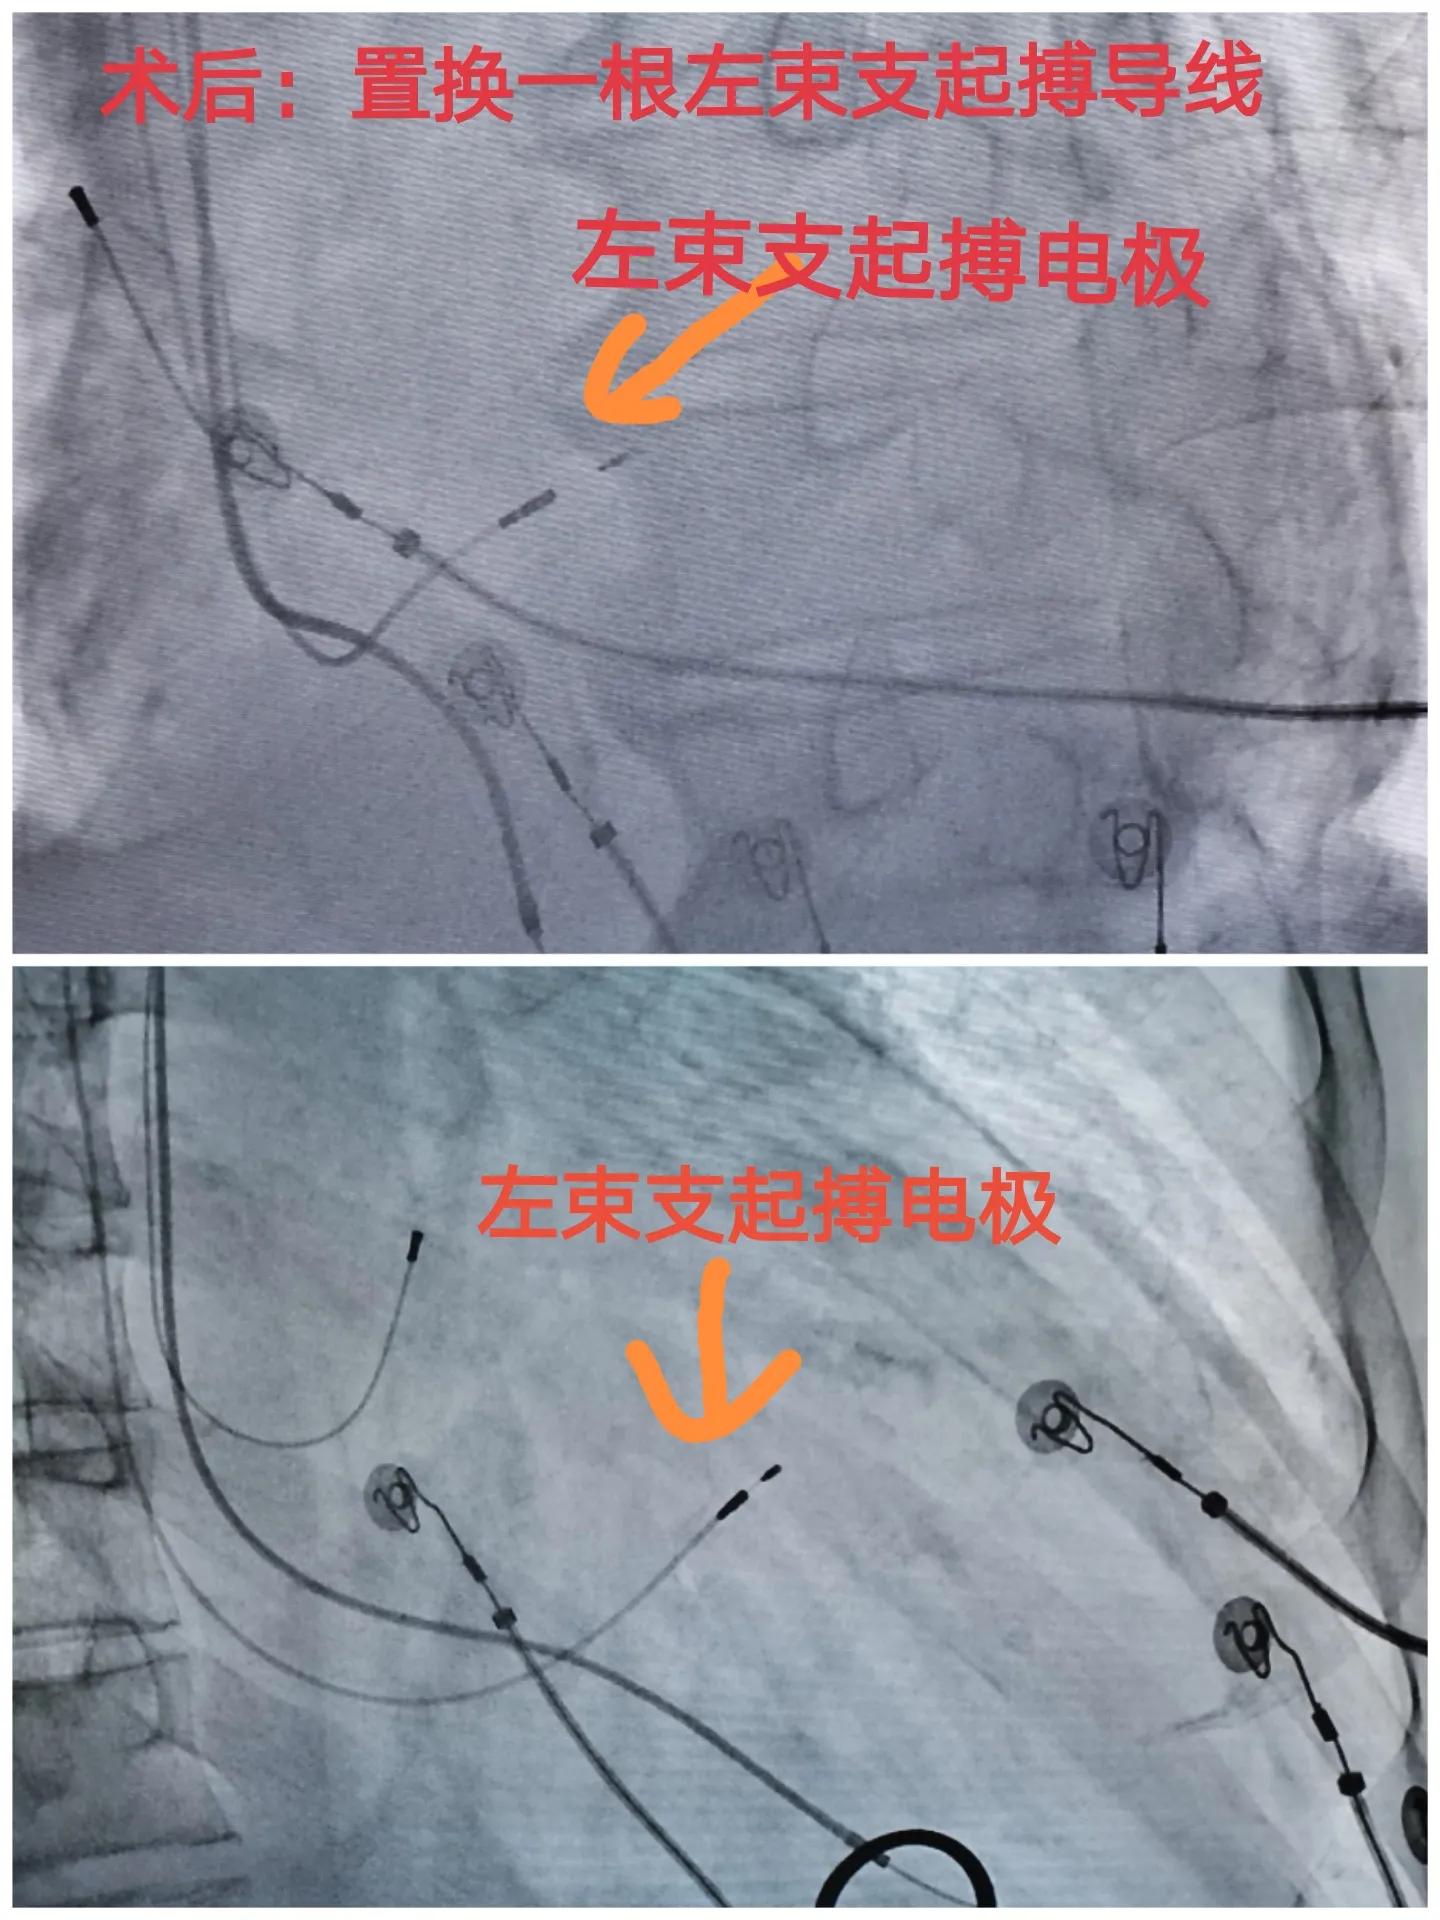

(二)起搏器电极更换手术顺利:

我们尝试左束支起搏,术中顺利,依次找到His,定位到左束支。

纯左束支起搏的QRS宽度为144ms,通过调整AV间期后,QRS宽度进一步减少至104ms,窄的令人感动!

就是通过调整起搏器电极就达到/超过了CRT的效果。